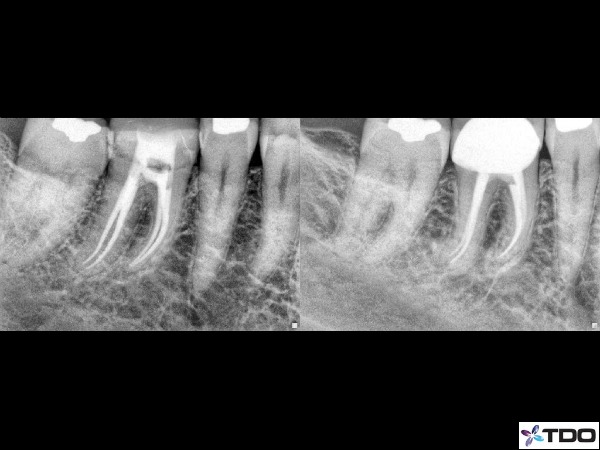

Case 1: Post Op and 1 year Recall

1) Patency. The most important feature of the root canal system is often the apical terminus or the last several mm within a root canal. The apical terminus is where most of the lateral anatomy is found and where an endodontic infection communicates with the peri apical bone. Patency is the concept of maintaining a small file to or just slightly beyond the apical foramen throughout the endodontic procedure. I usually use an eight or ten file to maintain patency in a canal. After every step of instrumentation, I go back to my ten file and ensure that the file reaches the apical terminus. In doing so, we maintain a glide path down the root and prevent apical ledging or blocked canals.

2) Don’t rush to instrument the apex. After patency is achieved we want to ensure we can passively take files to the apex without too much stress on our files. This often involves instrumenting to the apex with a 15-20K hand file before the introduction of rotary files. I would strongly recommend taking a 20 hand file to length prior to any rortary instrumentation. If a rotary file encounters resistance when progressing apically, I will often re-instrument with hand files or go back to the preceding rotary file before pushing onward. Adequate coronal enlargement can also be helpful although we want to avoid removing too much coronal dentin and compromising the strength of the tooth. I rarely use anything beyond a three gates for coronal enlargement.

There are very subtle twists and turns throughout a canal system. If we are not careful a ledge or block is easy to create especially in the last few millimeters of a canal system. Placing a small bend on a hand file can be very helpful to capture that elusive apical anatomy that can be so crucial to the success of a case. The small bend can also help slip into a canal system that splits from one main canal into two.